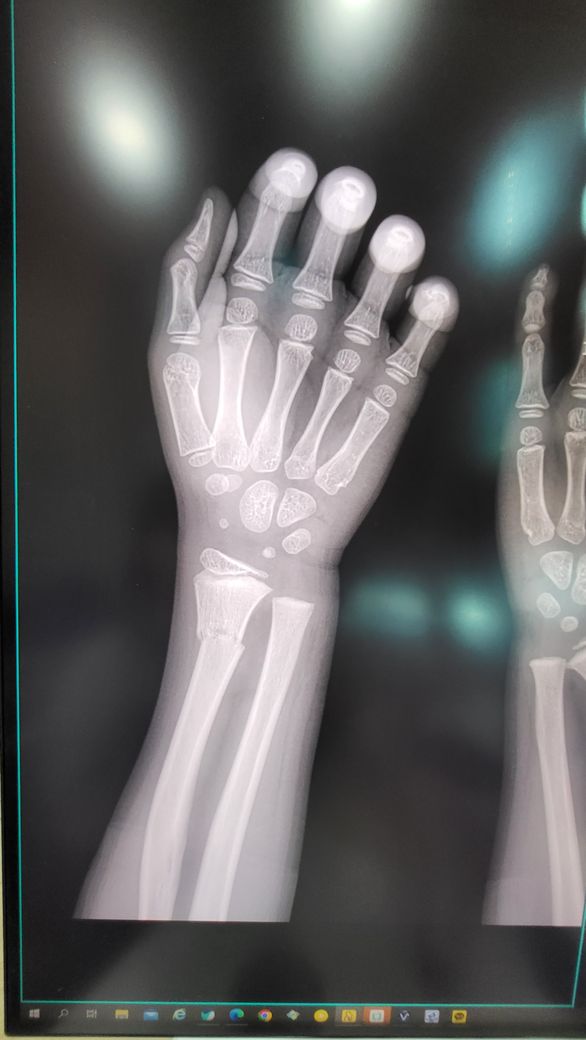

8살 아들 11월 14일 팔목골절

반깁스ㅡ 통깁스 ㅡ반깁스 한달 하고 깁스 푸른지 2주정도 지났습니다

뼈는 제자리 잘 찾아생긱골진도 생기고 했다고 깁스 풀면서 한달정도는 조심하는게 좋다고 들었는데 그냥 가벼운 줄넘기 같은건 해도 될지 궁금하네요